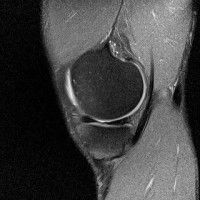

무릎 mri 간단히 봐주실 수 있으시나요 ㅠㅠ

안녕하세요 8년전 십자인대 수술하고 최근 무리한 운동에 무릎 불편감이 생겨서

mri 찍었습니다.

진단결과는 첫 찍은 병원에서 활액막염 이라는 진단을 받았습니다. 혹시 봐주실 수 있으실까요?

올라온 MRI가 단편적이라서 정확한 진단에 어려움이 있지만 십자인대에는 큰 이상이 있지는 않은것 같으며, 무릎관절내 물이 있는 것으로 보아 활액막염의 진단이 맞을 것 같습니다.

하지만 단편적인 영상이기 때문에 촬영병원에서 정확한 판독지 등을 받으시는 것이 좋겠습니다.